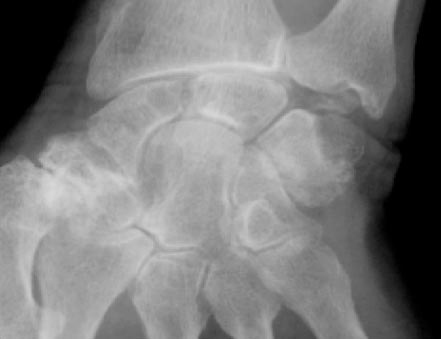

© La Revue du Praticien Radiographie de poignet gauche de face. Chondrocalcinose articulaire. Pincement de l'interligne radiocarpien. Pincement de l'interligne scaphotrapézien. Incrustation calcique du ligament triangulaire du carpe.